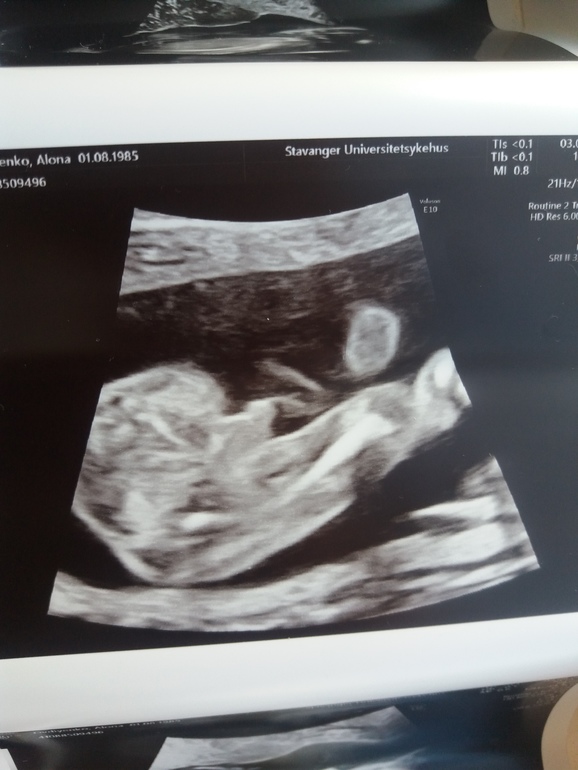

Бывают ли ошибки узи?Девочки посмотрите,у нас мальчик или девочка?

Всем большой привет!были на узи сказали что 85% мальчик.Я так ждала девочку,может ли быть ошибка?Второй мальчик,как же так.по всем календарям девочка,снится мне девочка,сын говорит что в животике сестричка.А на узи мальчик?

мы тоже надеялись на девочку....вот сказали на 19 недель мальчик то тоже думаем вдруг тот шнурочек это продолжение пуповину.....но торчит писюнька как на Вашем фото